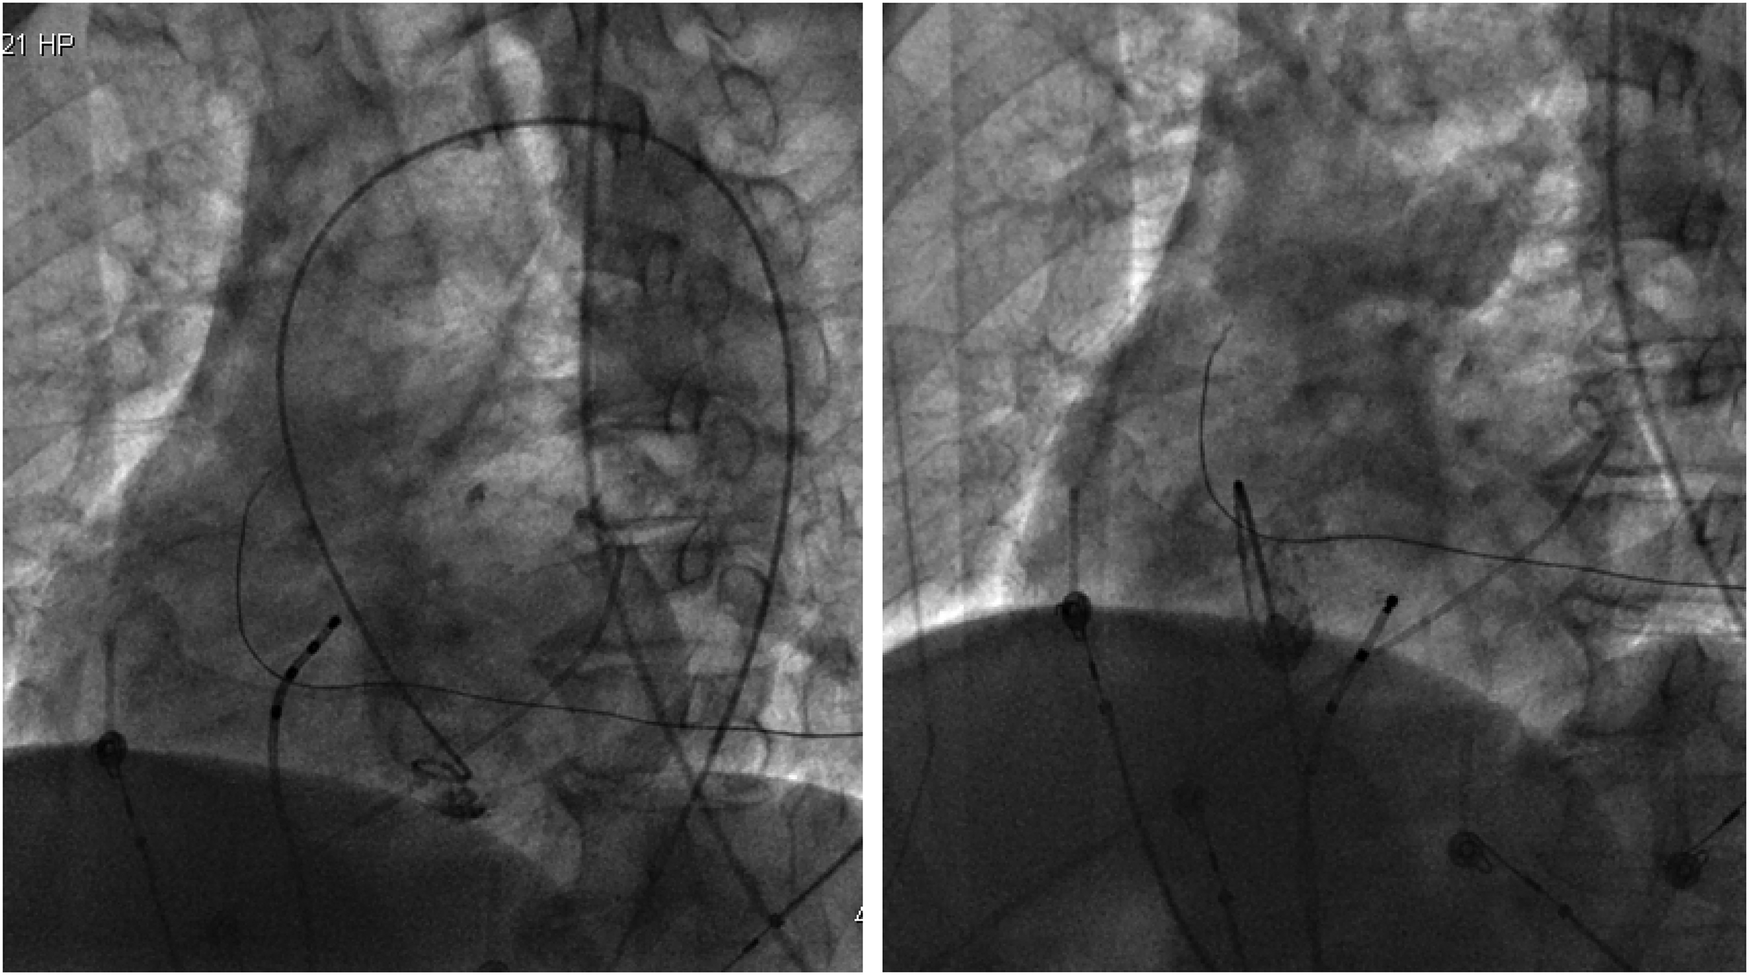

With the radiofrequency ablation power set at 30–40 W and the target temperature at 55 °C, the radiofrequency transmission lasted up to 90 s (Figure 2). During the ablation process, steam pop was not perceived, and there were no sudden changes in ablation parameters such as impedance、power or pressure values (Figure 2). After the termination of radiofrequency, the ventricular premature beats were significantly reduced. During the observation period after ablation (not immediately after), the patient suddenly complained of chest tightness, shortness of breath, and chest pain, and the blood pressure dropped to 102/65 mmHg (baseline blood pressure value: 149/78 mmHg). x-ray fluoroscopy observation showed a translucent shadow around the heart in the pericardial cavity (Figure 3), and the patient was suspected of having pericardial tamponade. Pericardial puncture and drainage were immediately performed. After slowly withdrawing 150 ml of bright red blood, no more blood was withdrawn, and the patient's blood pressure gradually recovered and tended to be stable. The ACT value immediately before pericardiocentesis was 126 s. Protamine was not administered and no additional heparin was administered due to the short duration of ablation. The unexpectedly low ACT at the time of pericardiocentesis may reflect partial heparin metabolism and consumption. Blood gas analysis of the red blood cells drawn from the pericardium suggested arterial blood. Under fluoroscopy, the translucent zone around the heart was smaller than before. In order to further clarify the perforation site, angiography was performed in the left and right ventricles(Supplementary Videos S1–S4), and it was found that the contrast agent did not extravasate outside the cardiac cavity (Figures 4A,B). Bedside transthoracic echocardiography showed that the pericardial effusion did not further increase. After indwelling the pericardial drainage tube, the patient was returned to the cardiac care unit for further observation. After 1 day of continuous drainage, no effusion was drained, and continuous review of echocardiography showed no obvious effusion (Supplementary Figures C,D). The patient was discharged after the drainage tube was removed.

Figure 4

(Left) Left ventricular angiography showing no contrast agent extravasation into the pericardial cavity. (Right) Right ventricular angiography showing no contrast agent extravasation into the pericardium.